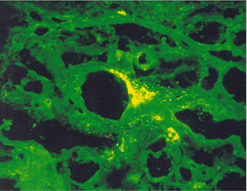

임상증상4

사진41 사진42

설명41 설명42